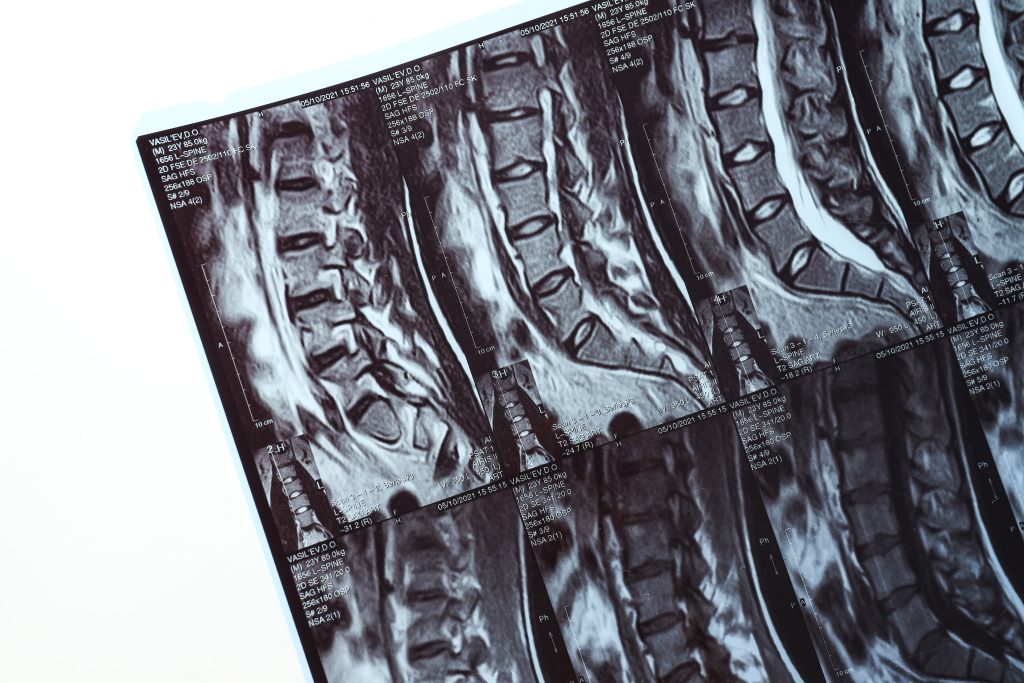

A medicina diagnóstica evoluiu significativamente nas últimas décadas, permitindo avaliações mais precisas e tratamentos mais eficazes. No campo da ortopedia, a ressonância magnética se destaca como um dos exames mais avançados para a análise das estruturas musculoesqueléticas.

Mas o que faz desse exame o padrão ouro no diagnóstico ortopédico? A seguir, exploramos os principais motivos.

A ressonância magnética utiliza um campo magnético e ondas de rádio para criar imagens de alta definição das estruturas internas do corpo. Diferentemente do raio-X e da tomografia computadorizada, que são mais eficazes para visualizar ossos, esse exame se destaca na análise de tecidos moles, como:

Essa capacidade de capturar detalhes essenciais torna a ressonância magnética indispensável na identificação de lesões ortopédicas complexas.